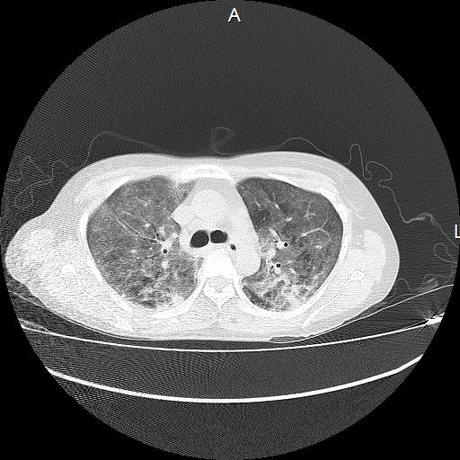

El parénquima pulmonar con areas parcheadas difusas en vidrio despulido combinadas con otras areas hipodensas de baja atenuación debidas a atrapamiento aéreo y engrosamiento intersticial y zonas de fibrosis de predominio en lóbulos medios e inferiores de ambos pulmones.

- LOS HALLAZGOS PUEDEN ESTAR EN RELACIÓN A NEUMOPATIA INTERSTICIAL PROBABLE ETIOLOGIA HIPERSENSITIVA VS AUTOINMUNE/BACTERIANA/FUNGICA.